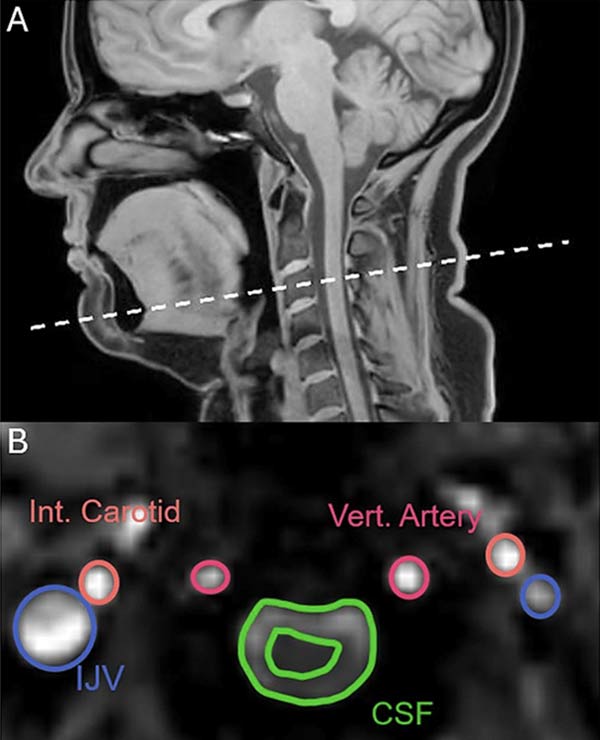

به نقل از Sciencealert، در این مطالعه، تیم تحقیقاتی با بهره‌گیری از تصویربرداری ام‌آر‌آی، سر و گردن ۲۲ داوطلب سالم را در شرایط مختلف بررسی کردند؛ شرایطی که شامل خمیازه کشیدن، تنفس عمیق، فروخوردن خمیازه و تنفس عادی بود.

از آنجا که خمیازه کشیدن و تنفس عمیق از نظر مکانیزم‌های فیزیولوژیکی شباهت‌هایی دارند، انتظار می‌رفت الگوهای ثبت‌شده در اسکن‌ها نیز مشابه باشند. با این حال، نتایج تفاوتی کلیدی را آشکار کرد: برخلاف تنفس عمیق، خمیازه کشیدن باعث می‌شود مایع مغزی‌نخاعی (CSF) از مغز دور شود.

تحلیل داده‌ها همچنین نشان داد که هم تنفس عمیق و هم خمیازه کشیدن، جریان خون خروجی از مغز را افزایش می‌دهند و در نتیجه فضای بیشتری برای ورود خون تازه فراهم می‌شود. با وجود این، جهت جریان خون در اثر خمیازه تغییر نمی‌کند. در مراحل ابتدایی خمیازه، جریان خون شریانی کاروتید به مغز تا حدود یک‌سوم افزایش می‌یابد؛ موضوعی که می‌تواند شواهدی از کارکردهای چندگانه این رفتار ارائه دهد.